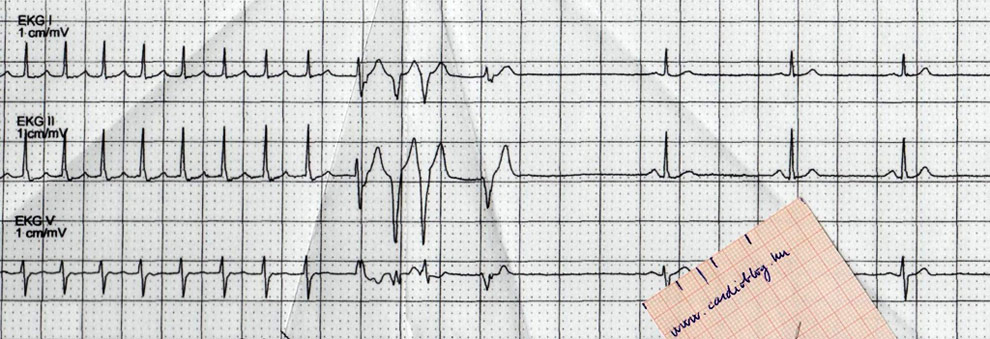

A panel bal oldalán az RR távolságok változása látható a scan időtartama alatt. A pitvarfibrilláció miatt az RR távolságok szabálytalan módon követik egymást. (Szabályos ritmus vízszintes vonalként ábrázolódna). Step-and-shoot felvételezési módot alkalmaztunk és a pirosan jelzett vastagabb szakaszok jelzik a felvételezés időpontjait. A jobb oldali panel az EKG jelet mutatja. Az arrhythmia detekciós algoritmusnak köszönhetően a masodik lépést a scanner megismételte, mivel az systoles fázisra esett.